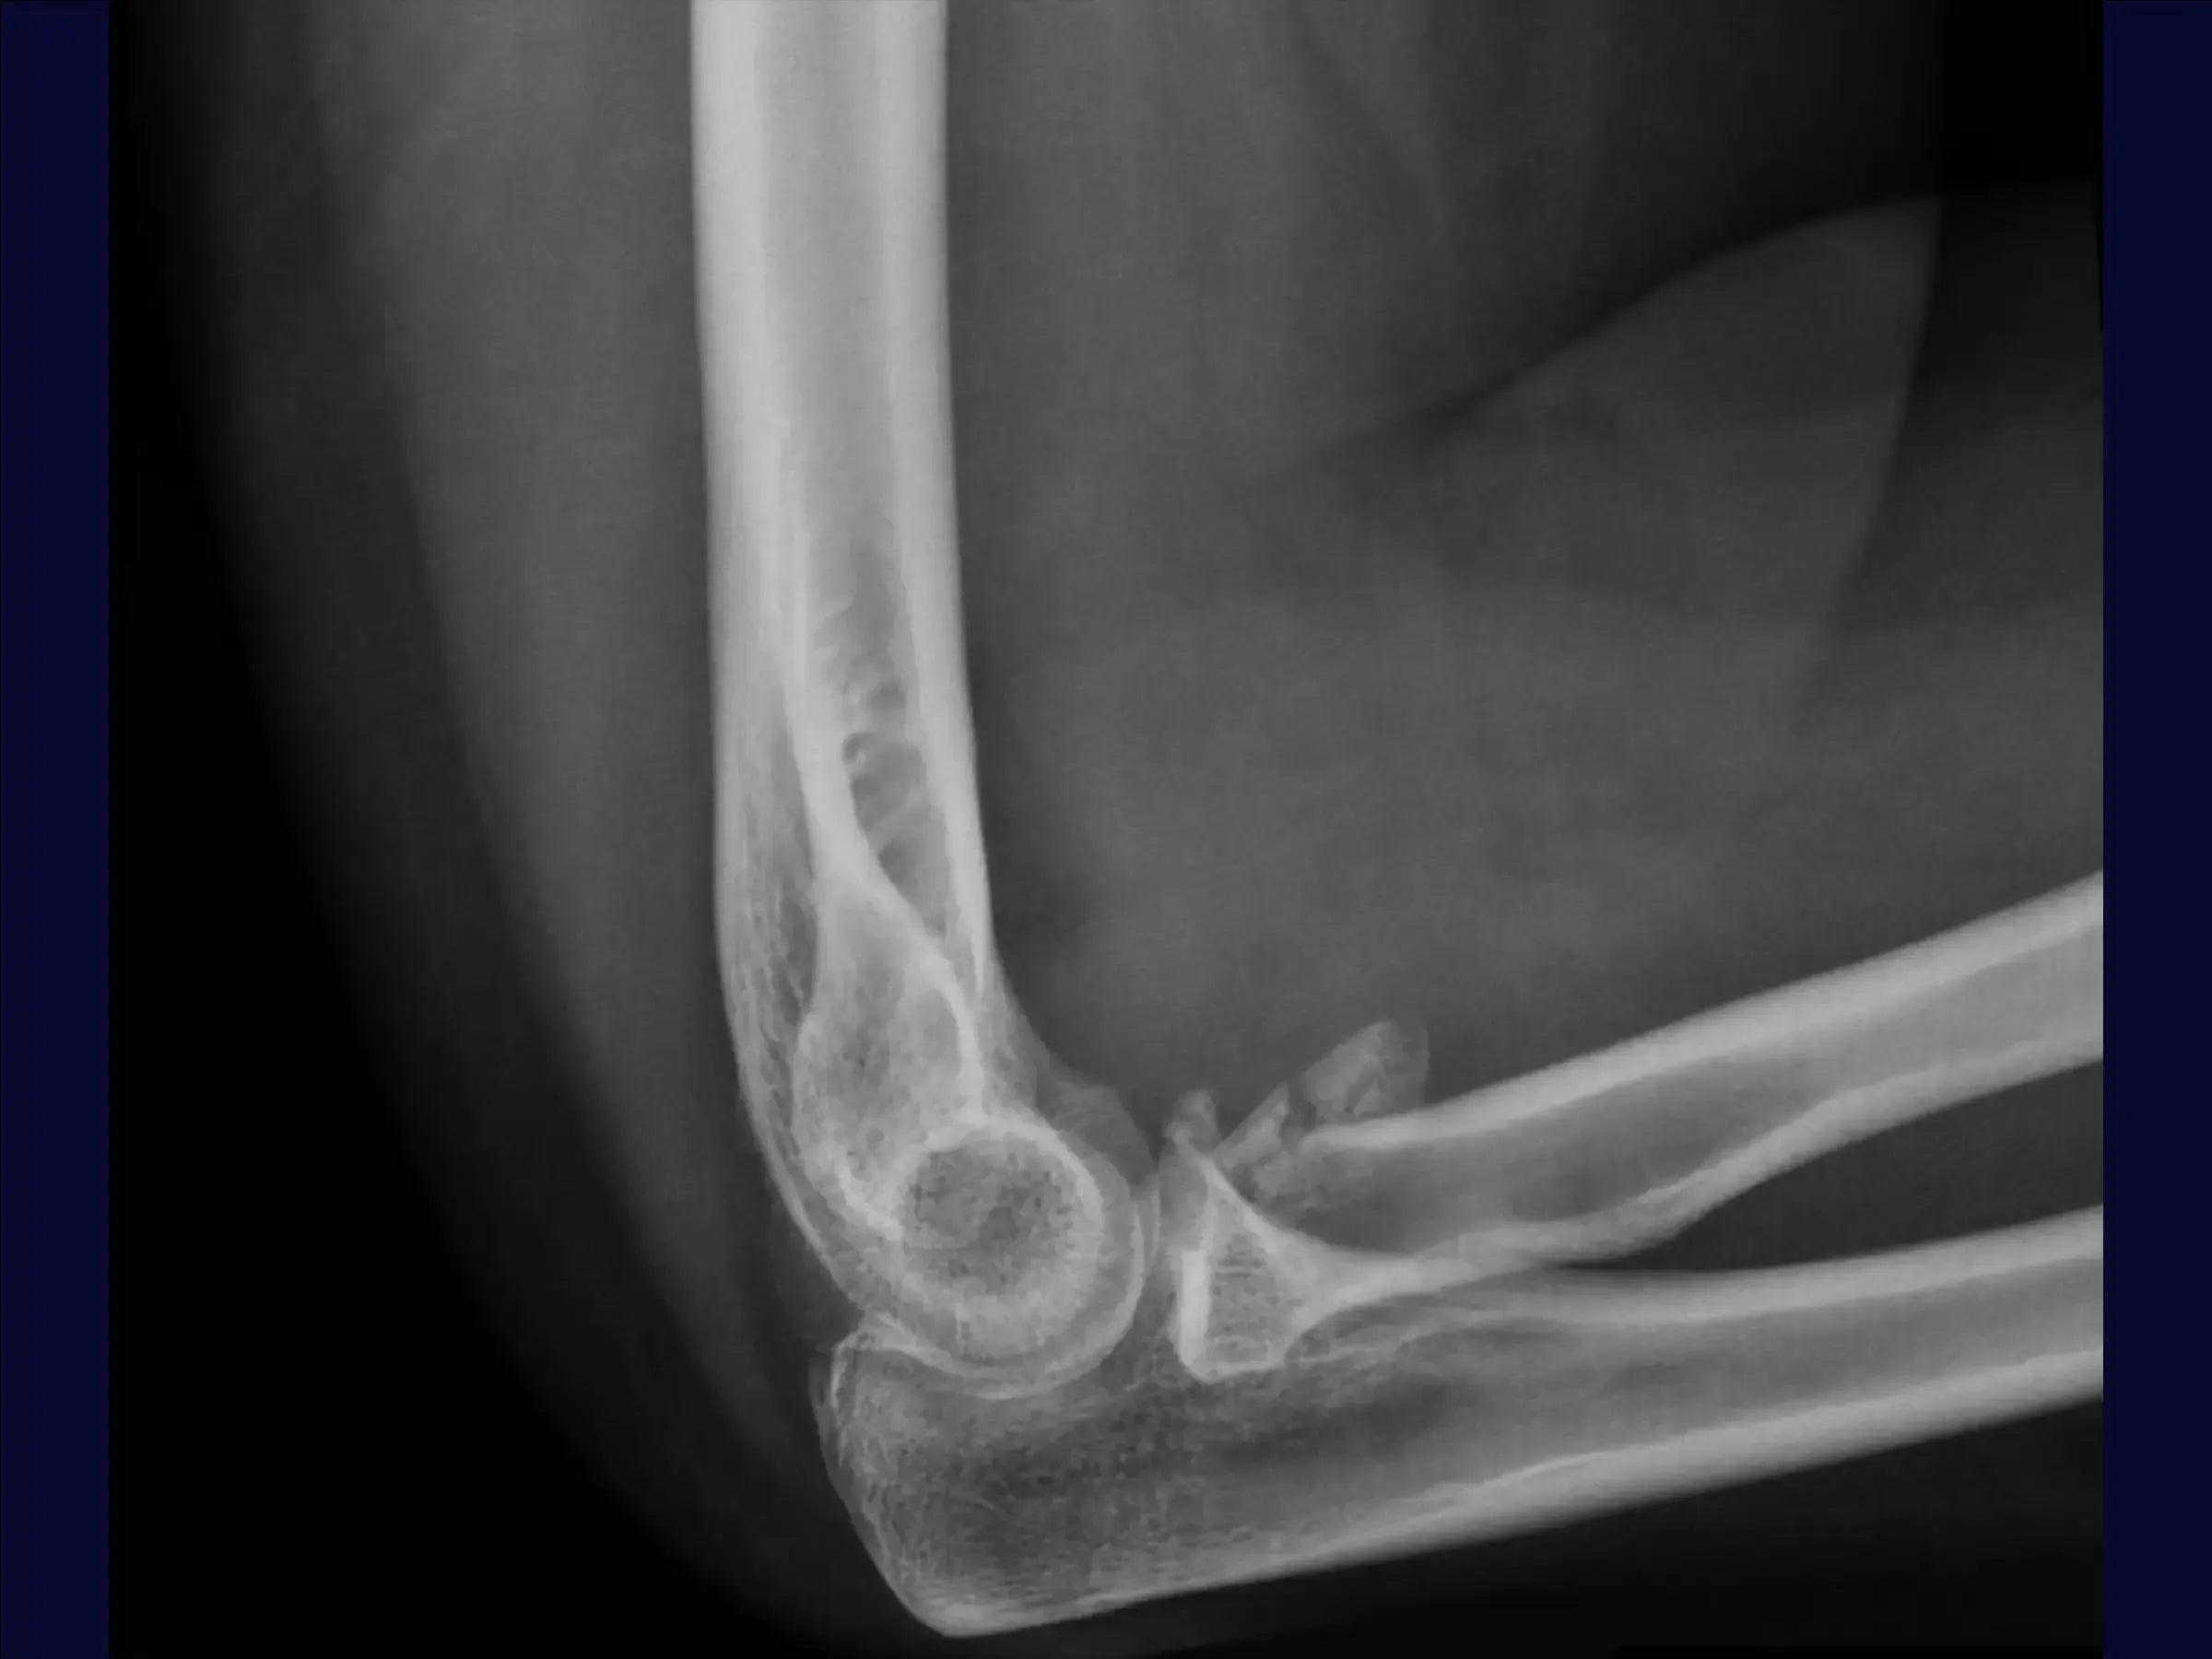

Reconstrucción de fractura multifragmentaria de cabeza radial (Mason 3) con inestabilidad asociada

Fracturas de radio (Mason 3): osteosíntesis y reparación de ligamentos para restaurar la función del codo.

Mejore sus habilidades en la reconstrucción de fracturas multifragmentarias de la cabeza radial, tipo Mason 3, asociadas con compromiso de la cápsula articular y fractura de la apófisis coronoides . Esta capacitación se centra en el abordaje quirúrgico que busca estabilizar la fractura mediante osteosíntesis , reparación integral de ligamentos y manejo posoperatorio temprano para restaurar la función del codo.

- Evaluación y planificación inicial: Interpretar radiografías para identificar fracturas complejas (Mason 3) y compromiso articular. Planificar siempre la reparación del ligamento y tener una prótesis disponible como alternativa.

- Evaluación de la fractura : Decidir entre osteosíntesis o artroplastia según la respuesta del periostio a la tracción de los fragmentos.